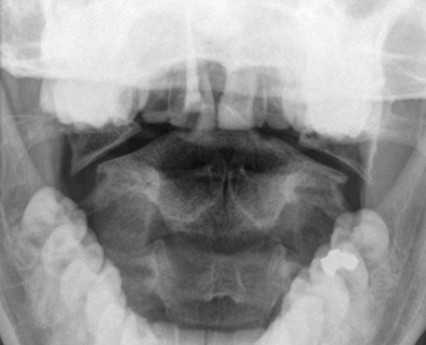

Перелом С1 Джефферсона. Рентгенография через открытый рот. С обеих сторон расширено расстояние от нижних площадок ножек С2 до боковых масс С1. Боковые массы С1 смещены латерально и перестают быть в линию с боковыми массами С1.

Обследование начинается со стандартной рентгенографии в 3 проекциях - боковой, передне-задней (прямой) и через рот.

Схема. Ход рентгеновского луча и расположение кассеты с пленкой при снимке через рот.

Если пациент находится в бессознательном состоянии, то рентгенография через рот невыполнима и заменяется КТ.